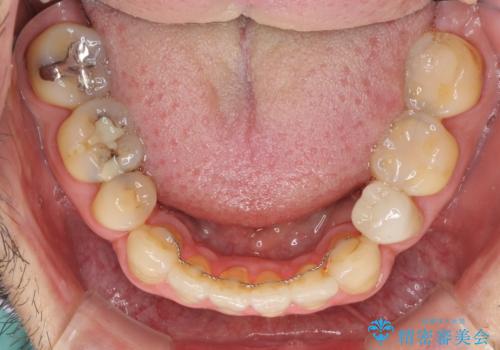

- むし歯による奥歯の痛みを気にして来院された患者様です。

神経にまでむし歯の及んでいる歯や、既に根管治療がされている歯に痛みがあったため、まずは根管治療を行うこととしました。

その後、以前行った抜歯矯正の後戻りをインビザライン・ライトにより改善し、むし歯や銀歯はオールセラミッククラウンにて補綴治療することとしました。